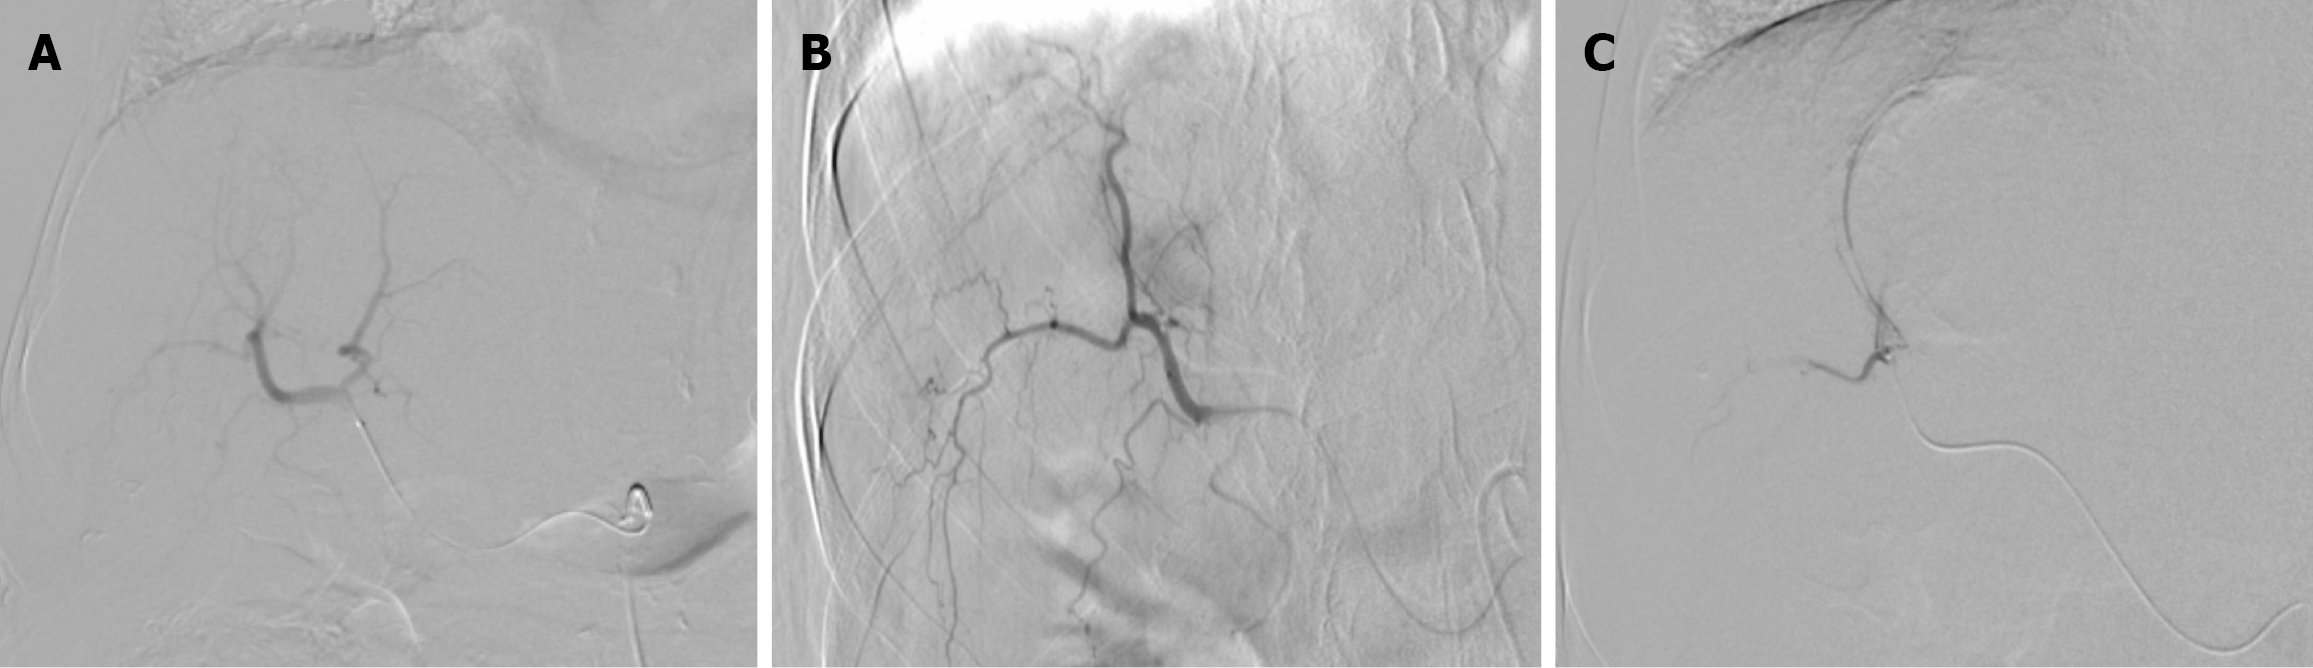

Figure 3 Digital subtraction angiography images during the first drug-eluting bead transarterial chemoembolization session in Case 1.

A: Right hepatic artery non-selective angiogram; B: Selective hepatic angiogram showed a hypervascular mass; C: Superselective angiogram demonstrated complete stasis of the vascular supply of the tumor after embolization.